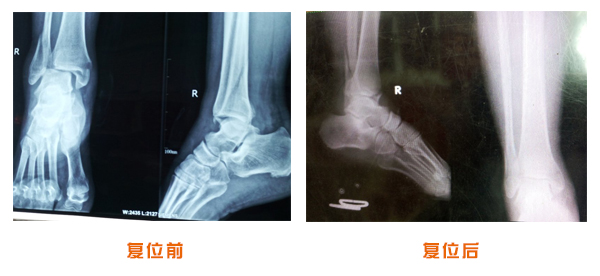

肥城市安駕莊梁氏骨科醫院是一所以梁氏手法正骨配合膏藥為特色的現代化??漆t院。

梁氏骨科術始創于清雍正年間,歷經八代,至今已有三百年歷史。據1929年泰安縣志載“梁瑞圖先生,字增生,號蓮峰,安駕莊人,精岐黃并發明接骨,凡跌打車凡跌打車軋皮不破而碎骨者......【詳細】 |